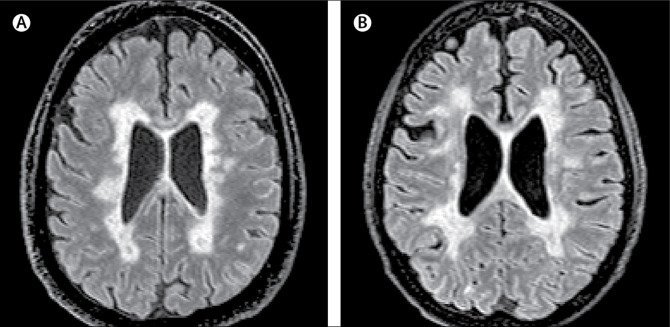

Niðurstaðan var sú að aðeins hópurinn sem var með hefðbundinn MS hafði skemmdir í hvíta efni heilans en báðir hóparnir höfðu dæmigerðar MS-skemmdir í mænu og í heilaberki. Þrátt fyrir að heilar MCMS-einstaklinganna höfðu ekki dæmigerðar MS-skellur í hvíta efninu mátti sjá þar minni þéttleika taugafrumna og þynnri heilabörk, eins og við dæmigerðan MS.

MCMS er óaðgreinanlegt frá dæmigerðum MS á þeim MRI-tækjum sem nú eru til, því í hluta taugafrumna hjá MCMS-einstaklingum má finna bólgur, sem líta út eins og dæmigerðar MS-skellur á MRI, en eru án niðurbrots mýelíns. Með nútímatækni er því aðeins hægt að greina MCMS eftir andlát.